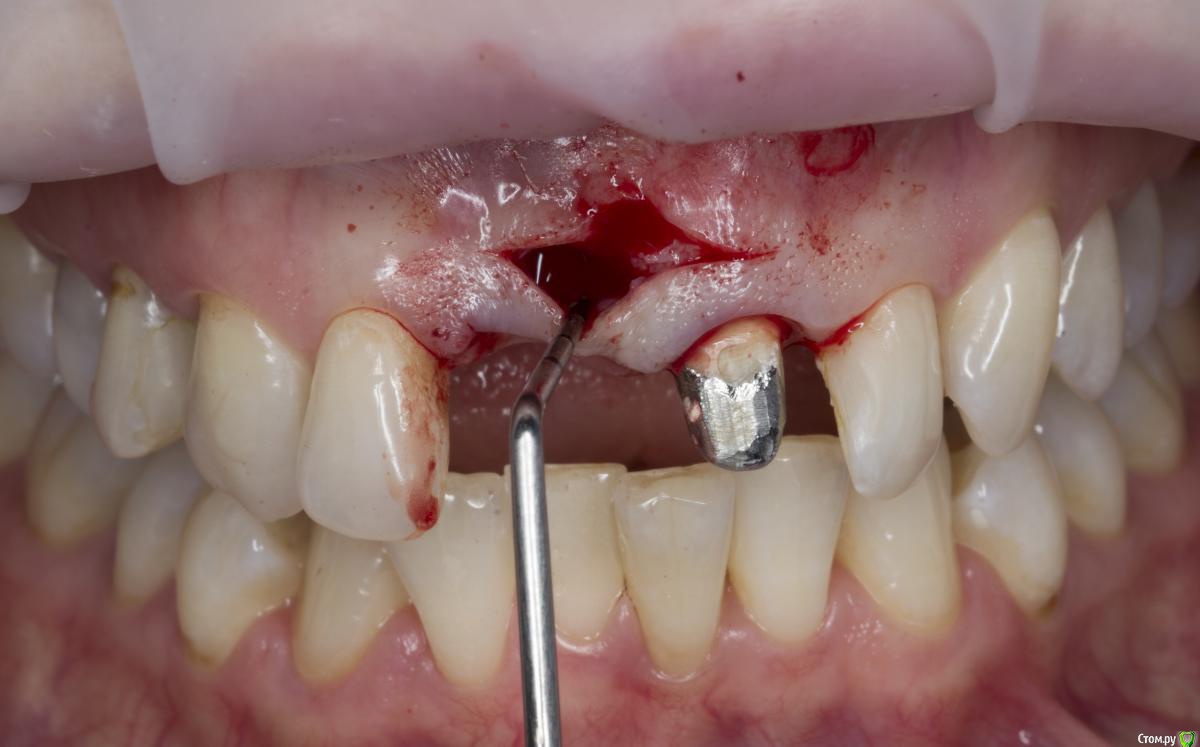

Александр07 Опубликовано 2 мая, 2020 Поделиться Опубликовано 2 мая, 2020 Коллеги доброго дня Обратилась молодая пациентка , в районе 30, десневая улыбка, планируется пластика во фронте с целью увеличения высоты сосочков, ну и объём можно немного добавить1.1 импл, сосочек 2.1-2.2 тоже ушёл от предыдущих операций, Раздумываю какой метод выбрать, есть несколько вариантовСклоняюсь к методу по Цуру - создание туннеля и подтянуть транс швами за межзубные контакты Вторым вариантом методика Сузуки но объём тогда вестибулярно не затронемИ по Зукелли , но опасаюсь осложнений в виде рубцов и т д, Кто что посоветует) Ссылка на комментарий

Александр07 Опубликовано 26 июня, 2020 Автор Поделиться Опубликовано 26 июня, 2020 Коллеги, скидываю фото проделанной работы, прошло около 1.5 мес, есть результат, спасибо за помощь, если какие то замечания /советы есть пишите 4 Ссылка на комментарий